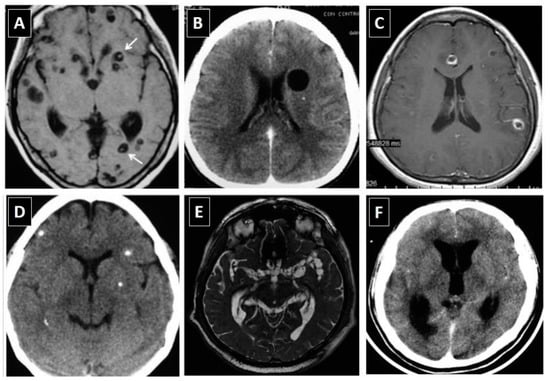

Cysticerci have variable appearance on neuroimaging studies [38]. In the brain parenchyma, parasites show different characteristics according to their involutive stage, which include: cystic lesions without enhancement (vesicular cysticerci), cystic or nodular lesions showing abnormal enhancement after contrast medium administration (colloidal and granular cysticerci), and small calcifications (calcified cysticerci). Parasites within the subarachnoid space may appear as cystic lesions that tend to group to each other’s (racemose cysticerci) or may present as a focal or diffuse arachnoiditis that most often involve the Sylvian fissure or the basal CSF cisterns, which are frequently associated with obstructive hydrocephalus. Ventricular cysticerci appear as lesions with different signal properties than the ventricular fluid that distort the anatomy of the ventricular system causing asymmetric hydrocephalus (scolices may be visualized in some of these cysts). Spinal cord cysticerci appear as nodular or cystic lesions if they are located intramedullary or as a focal or diffuse spinal arachnoiditis with or without cystic lesions if located in the spinal subarachnoid space. Figure 1 depicts the most common neuroimaging characteristics of cysticerci within the CNS. Of all these lesions, the only pathognomonic appearance is the presence of vesicular cysts showing the scolex as an eccentric brilliant point (the “hole-with-dot” imaging); however, even in these cases, some cystic tumors may have remnants of neoplastic cells in the interior of the cystic component resembling a scolex (pseudo-scolices). This warning note is of special importance for patients with a single parenchymal brain cyst.

Figure 1.

Neuroimaging characteristics of neurocysticercosis: (A) Parenchymal vesicular cysts showing the scolex (arrows) in T1-weighted MRI; (B) Vesicular cyst without scolex in contrast-enhanced CT scan; (C) Colloidal cysticerci appearing as ring-enhancing lesions in gadolinium-enhanced T1-weighted MRI; (D) Parenchymal brain calcifications in non-enhanced CT scan; (E) Multilobulated (racemose) subarachnoid cysticerci in FIESTA sequence MRI; and (F) Abnormal enhancement of basal leptomeninges and hydrocephalus in contrast-enhanced CT scan (Reproduced from Del Brutto et al, J Neurol Sci 2017, 371, 202-210) Copyright: the authors).